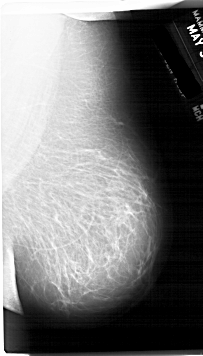

A_1759_1.LEFT_CC

LEFT_CC LINES 6436 PIXELS_PER_LINE 3646 BITS_PER_PIXEL 12 RESOLUTION 43.5 OVERLAY

FILE: A_1759_1.LEFT_CC.OVERLAY

TOTAL_ABNORMALITIES 1

ABNORMALITY 1

LESION_TYPE MASS SHAPE OVAL MARGINS CIRCUMSCRIBED

ASSESSMENT 3

SUBTLETY 4

PATHOLOGY BENIGN

TOTAL_OUTLINES 1

BOUNDARY